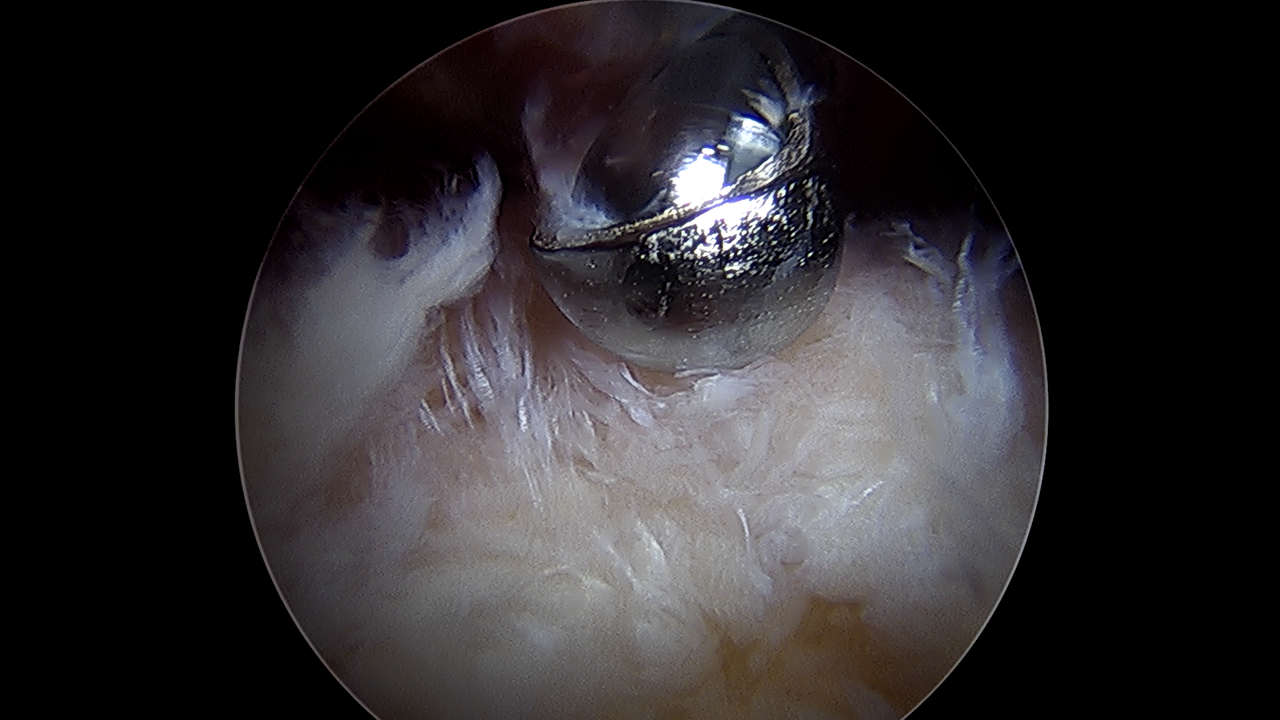

리제네텐은 관절내시경을 통해 손상된 회전근개 위에 콜라겐 패치를 덮어 조직이 자연스럽게 재생하도록 돕는 혁신적인 어깨 수술법입니다.

이를 통해 약 2mm의 새로운 회전근개 성장을 유도합니다.

한번 손상된 힘줄은 자연적으로 회복이 어려운데, 리제네텐 수술을 통해 재생을 유도하여, 기능 회복을 돕고 재파열 위험이 감소했습니다.